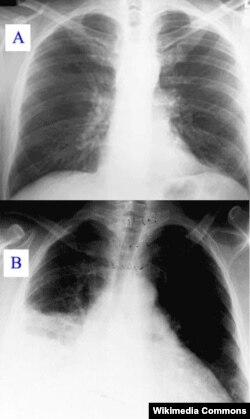

X-ray showing clear (A) and pneumonia infected lungs (B)

Once it gets in a person's lungs, the alveoli, or air sacs that take in oxygen, swell and fill up with fluid. This makes breathing difficult and painful, and can also limit the amount of oxygen a person takes into their body with each breath. It also causes fever, chills and coughing.